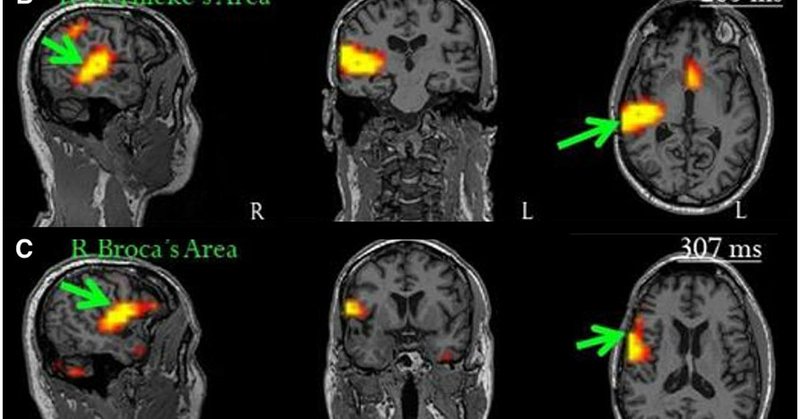

At @PittNeurosurg our approach to brain tumor care reflects a new level of sophistication—precise anatomical planning, preservation of cognitive function, and multidisciplinary decisions on every case. @pascalzinn @balzjr @amelia_stepniak @gecicinn https://t.co/KfESQb2ZO9

The gold standard for preserving language and cognitive function during complex brain tumor resection is direct electrical stimulation (DES) during awake cra...